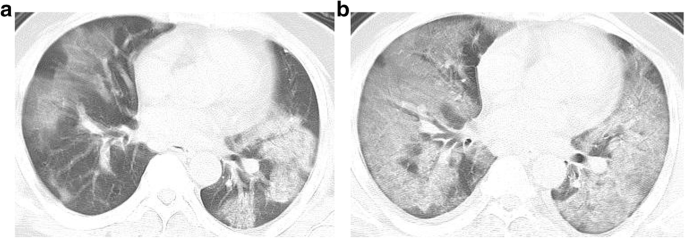

There were 14 cases (10.7%) with unilateral lung disease and 116 cases (89.3%) with bilateral lung disease. The NCP was classified for the first time according to the imaging distribution: there were 99 cases (76.1%) of lobular distribution (Fig. 1a), 102 cases (78.4%) of subpleural distribution (Fig. 1b), and 8 cases (6.1%) of diffuse distribution (Fig. 1c). These types can overlap in one patient.

The diagram and CT images of the NCP classified according to its imaging distribution. a Lobular distribution, (b) subpleural distribution, and (c) diffuse distribution